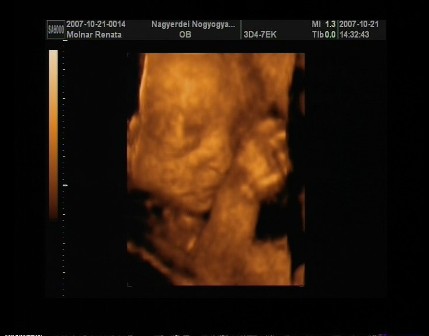

Egézséges kislányom lessz!Néhány fotó!!!! Kép Kép Kép Kép

m. reni

Nagyon jó képek! Annyira édes ahogy dörzsöli a szemét!!! :wink:

Neked pedig a baba fotók nagyon édik! Már alig várom , hogy mi is menjünk!